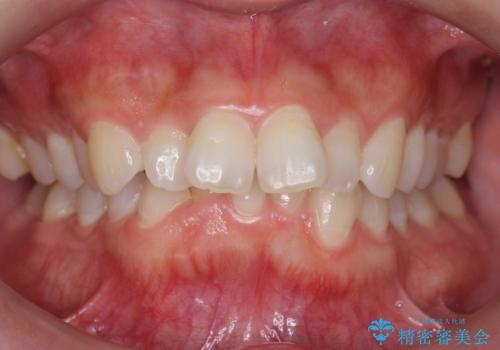

前歯をさげたい 歯を抜かずに マウスピース矯正で治したい

[ インビザライン矯正 ]マイクロインプラント用いた大きな遠心移動

担当医 大元洋佑